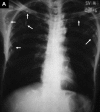

Subcutaneous cysticercosis